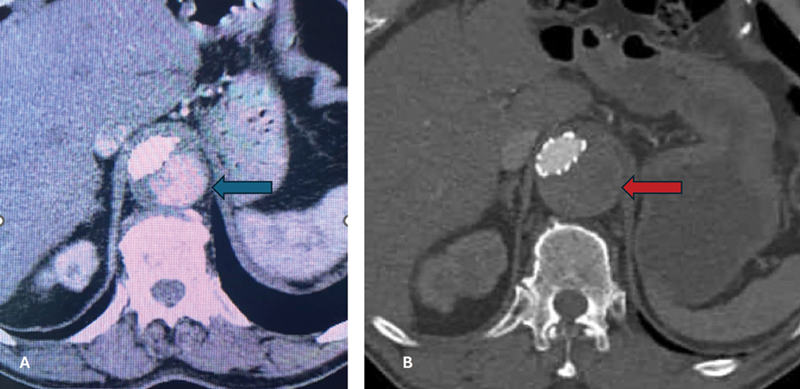

众所周知,脊髓缺血(SCI)是胸腹主动脉开放性和血管内修复术的并发症之一。围手术期增加脊髓灌注的措施,包括允许性高血压和放置腰椎引流管以控制脊髓压力,通常用于降低脊髓缺血的风险。围术期减少脊髓易受缺血性损伤的其他措施包括低体温、类固醇和输注纳洛酮。大多数病例会在手术后立即或数天内显现,并在采取上述措施后得到改善。我们描述了胸腔内血管主动脉瘤修复术后 20 个月出现延迟性 SCI 的罕见病例。

Spinal cord ischemia (SCI) is a well-known complication of both open and endovascular repair of the thoracoabdominal aorta. Perioperative maneuvers to increase spinal cord perfusion, including permissive hypertension and lumbar drain placement to control spinal pressure, are commonly used to reduce the risk of SCI. Additional perioperative measures to reduce the susceptibility of the spinal cord to ischemic insult include hypothermia, steroids, and naloxone infusion. Most cases manifest immediately or within days of surgery and improve with the aforementioned maneuvers. We describe a rare occurrence of delayed SCI 20 months after thoracic endovascular aortic aneurysm repair.